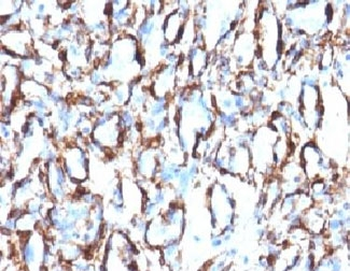

Immunofluorescent staining of fixed human HeLa cells with Smooth Muscle Actin antibody (clone SPM332, green) and NucSpot nuclear stain (red).

IHC: Formalin-fixed, paraffin-embedded Leiomyosarcoma stained with Smooth Muscle Actin antibody (clone SPM332).